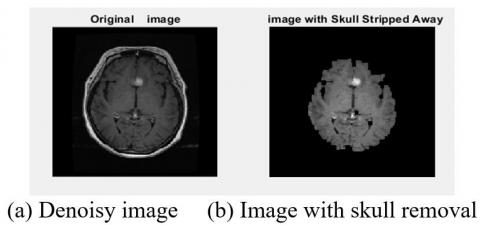

The second step of pre-processing was to remove the skulls of the extra areas. This was used to increase the speed and accuracy of segmentation detection. The skull removal results have been shown in Figures 10 and 11.

Figure 10. Skull removal results

Figure 11. Skull removal results

The images were recovered after the pre-processing noise removal and skull removal. Finally, the area of interest (ROI) in MRI images was examined to identify the tumor area in Figure 12.